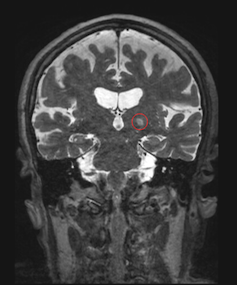

One rare disease of particular interest for my lab is cerebral cavernous malformation, or CCM. CCMs are lesions in the brain that occur when the cells that make up blood vessels undergo uncontrolled growth. While uncommon, when these lesions grow and hemorrhage, they can cause debilitating neurological symptoms. The most common treatment for CCM is surgical removal of the brain lesions; however, some CCMs are located in brain areas that are difficult to access, creating a risk of side effects. Radiation is another treatment option, but it, too, can lead to serious adverse effects.

We found that using focused ultrasound to open the blood-brain barrier can improve drug delivery to CCMs. Additionally, we also observed that focused ultrasound treatment itself could stop CCMs from growing in mice, even without administering a drug. While we don’t yet understand how focused ultrasound is stabilizing CCMs, abundant research on the safety of using this technique in patients treated for other conditions has allowed neurosurgeons to begin designing clinical trials testing the use of this technique on people with CCM.